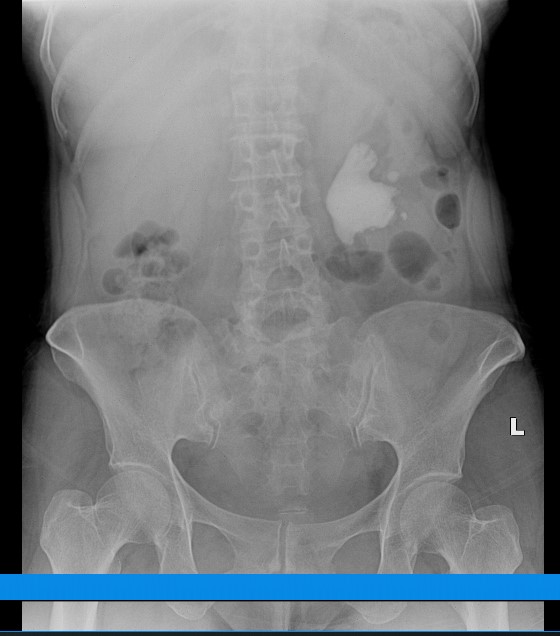

Xác định tình trạng của bệnh nhân nếu không được điều trị sẽ gây ra những biến chứng như: Viêm thận, ứ nước thận và đặc biệt là suy thận, các bác sĩ Khoa Ngoại thận tiết niệu và Nam học quyết định thực hiện tán sỏi qua da đường hầm nhỏ. Kíp thực hiện đã tiến hành rạch da khoảng 0,5cm vùng thắt lưng, tạo một đường hầm nhỏ từ ngoài da vào thận, đưa máy nội soi qua đường hầm tìm sỏi. Sau đó quan sát thấy 1 viên sỏi bể thận trái rất cứng và lớn, kích thước 5×6 cm, hình xù xì như san hô ở bể thận và đài thận. Nhanh chóng sử dụng tia Laser tán vỡ sỏi thành từng mảnh nhỏ và hút các mảnh sỏi vỡ ra ngoài qua đường hầm. Kiểm tra phim chụp sau mổ đánh giá, người bệnh đã sạch sỏi so với phim cũ, sức khỏe ổn định, tinh thần thoải mái và đã được xuất viện.